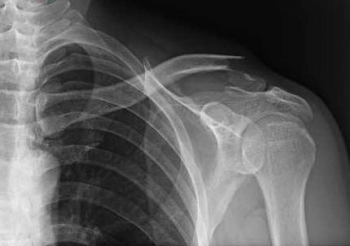

今日、ご紹介するのは、鎖骨の骨折についてご紹介していきたいと思います。

鎖骨骨折

鎖骨骨折は、とても発生頻度が高く、転倒し、肩・肘・手を突いた際に介達外力によるものが多いです。

鎖骨でもっとも骨折しやすい場所は、力学的に弱い中外1/3の境界部です。

直達外力での骨折はまれですが、発生した際、外1/3部(外端部)に発生が多いです。